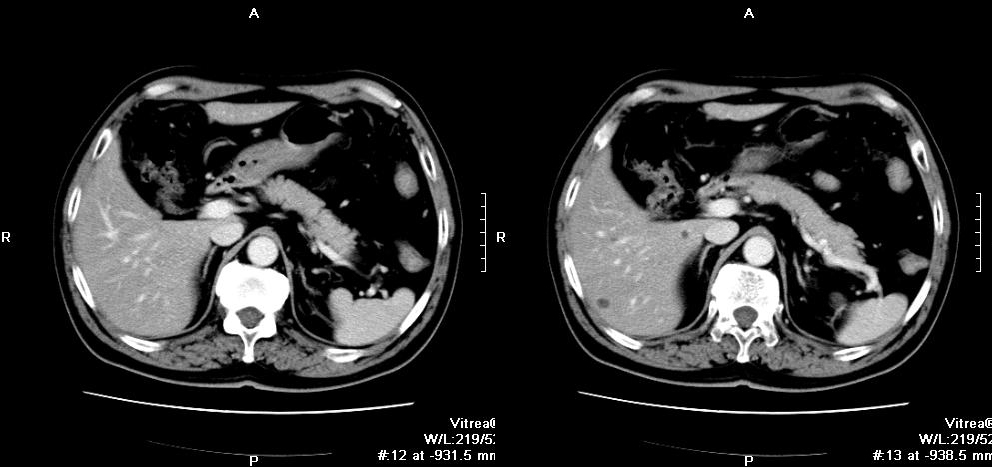

3.CT掃描:對(duì)診斷腎上腺囊腫有重要價(jià)值,可明確腫塊為囊性還是實(shí)質(zhì)性,可查出5mm以上的腫塊。腎上腺真性囊腫為圓形或橢圓形,邊緣光滑,密度與水相仿.CT值為0~20Hu,周圍繞以密度較高的薄壁,約有15%的上皮性囊腫可出現(xiàn)殼樣鈣化改變。假性囊腫囊壁較厚,出血或感染時(shí)囊腫密度不均,CT值增高。寄生蟲囊腫表現(xiàn)為囊腔內(nèi)有分隔改變。